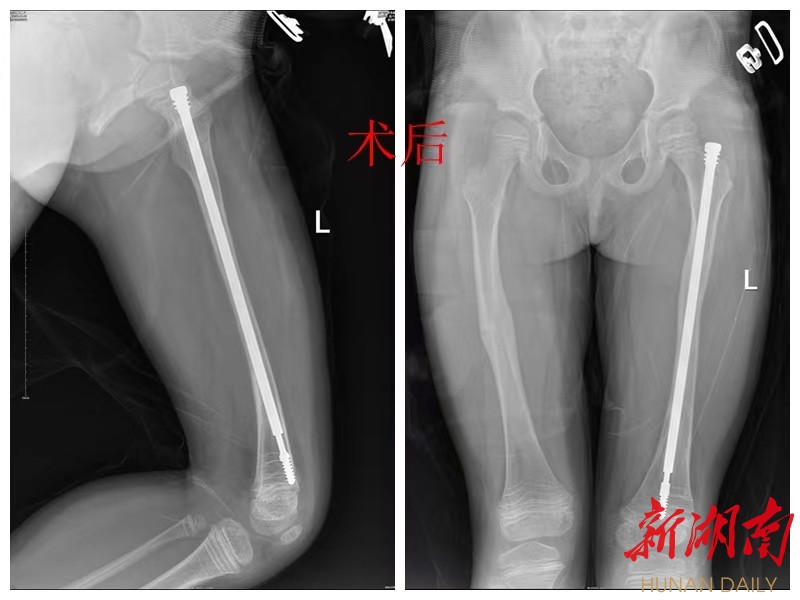

一筹莫展之际,小雅家人意外获悉娄底市骨伤医院小儿骨科擅长于小儿先后天畸形疾病的诊治,于是马不停蹄前来求诊。该院小儿骨科副主任医师胡世密接诊后,经过体查及拍片发现小雅左股骨弯曲成角畸形且直径非常细小、左下肢缩短3厘米、全身骨骼骨密度减低并轻度变形,胸腰椎体扁平呈楔形改变。经小儿骨科主任彭放兵、副主任医师胡世密等专家集体讨论诊断小雅为成骨不全症,骨质相当脆,其左股骨多次骨折已弯曲畸形,髓腔闭塞,需要行截骨矫形手术,因为随着孩子年龄增长,骨骼长度增长,需要内固定长时间保护,所选择了可延长髓内钉固定治疗,内固定在髓腔内可随诊孩子骨骼增长而变长。

然而,给骨折的“瓷娃娃”做手术,就好比在鸡蛋上刻画,为避免术中造成“瓷娃娃”二次骨折,小儿骨科邀请麻醉科主任隆清、手术室护士长彭卫芬等专家团队进行术前大讨论。一切准备充分后,以彭放兵、胡世密为首的小儿骨科专家团队在麻醉科、手术专家的紧密配合下,历经3个小时小心谨慎操作,手术成功完成。

胡世密介绍说,过去由于得不到规范化治疗,“瓷娃娃”骨折后常常需要复位钢板内固定或外固定支架固定,术后再骨折发生率很高,容易致残,有的需坐轮椅甚至终生卧床。而可延长髓内钉技术通过放置合适的可延长髓内钉,可以有效地防止骨质弯曲并且可以伴随儿童生长发育自然延长,一次手术就可以达到不用更换内固定目的,加上使用磷酸盐制剂改善骨骼质量治疗,使患者骨骼畸形得到矫正的同时加强了骨骼的强度,减少再次骨折的发生,极大地改善患儿的生活质量,减轻了社会负担。